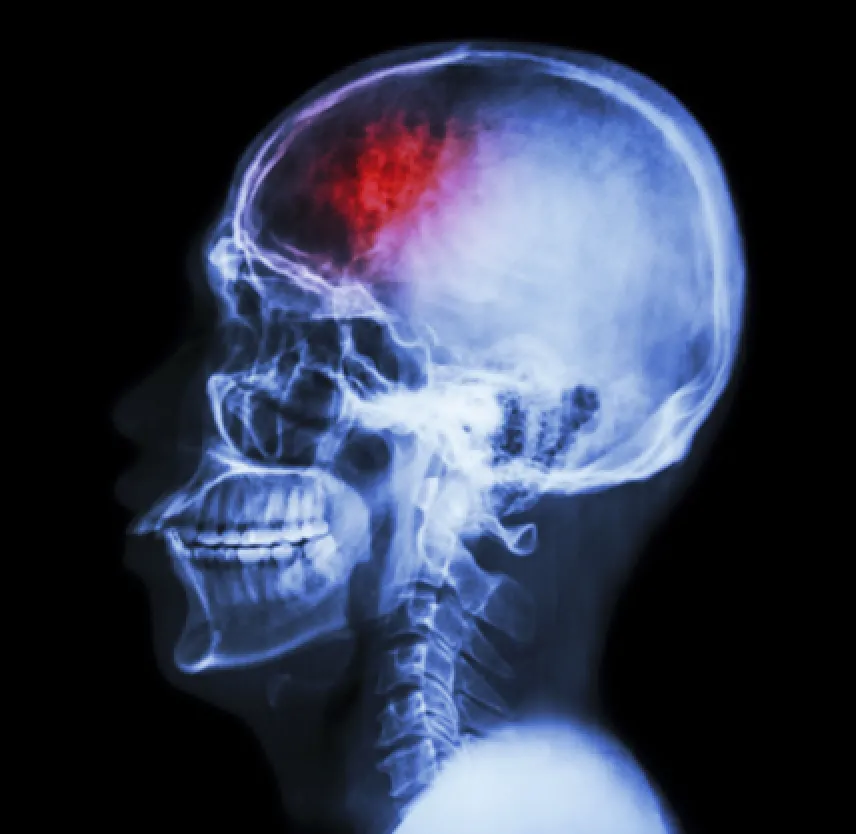

When you sustain a head injury, a host of symptoms can come into play. When you suffer a brain injury, those symptoms are more pronounced and more severe.

Some of the more common major signs of a brain injury following a car wreck:

Brain injuries require medical treatment. Doctors commonly use MRIs and CT scans to see if there is permanent damage or bleeding in the brain. Mild to moderate brain injuries are treated conservatively with medication and rest. Diuretics, anti-inflammation medicines, anti-seizure drugs and pain medication are used to alleviate symptoms. If there is bleeding in the brain or a skull fracture, surgery may be a life- saving option that doctors use for treatment.